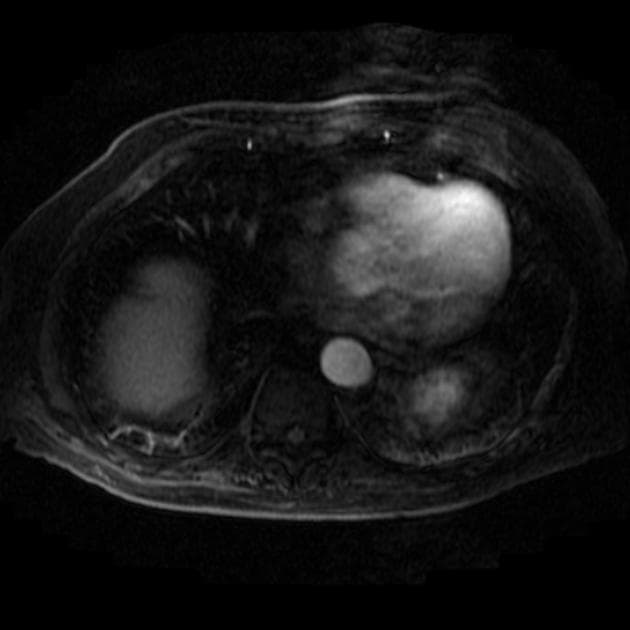

Axial C+ portal venous phase

- Thấy khối tăng quang dần qua thì cửa và thì muộn tại vị trí nối của ống mật gan phải và gan trái (Klatskin tumor).

- Tăng quang dần qua thì cửa và thì muộn (khoảng 15 phút sau tiêm thuốc cản quang) là đặc điểm của ung thư biểu mô tế bào gan đường mật (cholangiocarcinoma).

U Klatskin (Klatskin tumor)

- "U Klatskin là dạng ung thư biểu mô ống mật tại cửa gan, xuất phát tại vị trí nối ống mật gan phải và trái."

- "Đặc điểm hình ảnh điển hình là tăng quang dần và liên tục ở thì cửa và thì muộn trên CT hoặc MRI có tiêm thuốc cản quang."